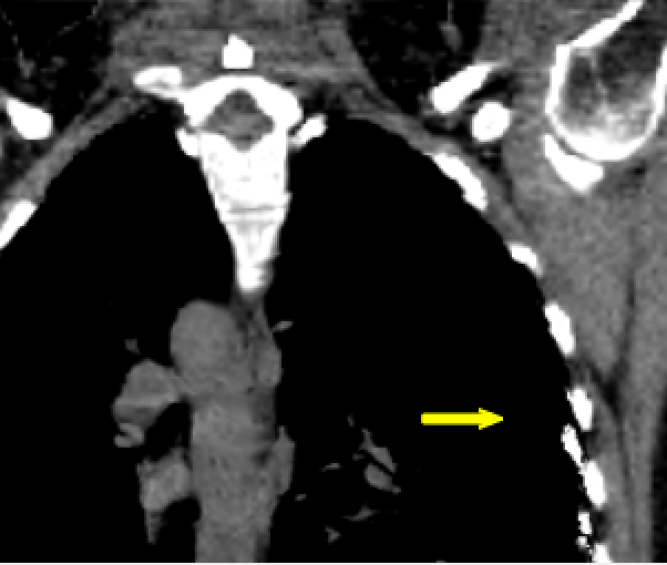

Figure 5: Upper thorax coronal views of the animated CT data of the patient pat3D𝑝𝑎𝑡3𝐷pat3D (a-d) deformed with the model of pat4D𝑝𝑎𝑡4𝐷pat4D. Rib artifacts are indicated by the yellow arrow in (c).

(a) First time point.

Refer to caption

(b) Second time point.

(c) Third time point.

(d) Fourth time point.